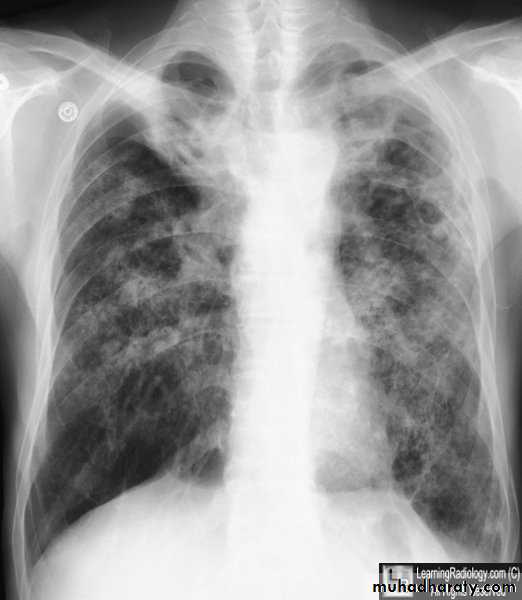

Interstitial pulmonary edema

Pulmonary edema ( alveolar pulmonary edema)

Bat wing sign ( alveolar pulmonary edema)

38.interstial pulmonary edema

39.pulmonary edema ( alveolar pulmonary edema )

40.batwing sign ( alveolar pulmonary edema )